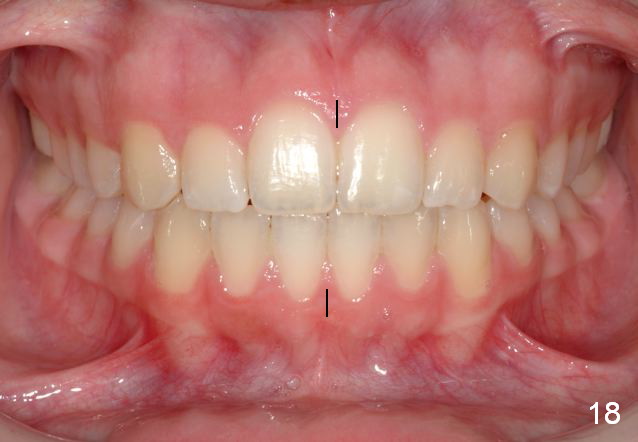

Final Results of Unilateral Class II Malocclusion

After using Rapid Molar Distalizer.  Total treatment lasts 50 months.